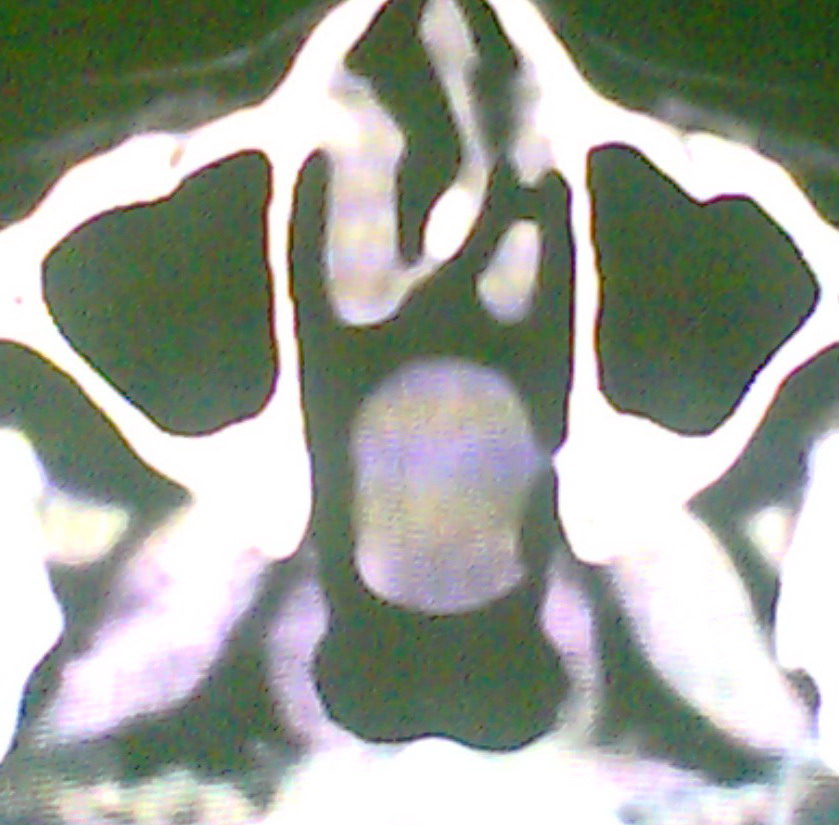

女、18岁,身高1.5左右,鼻塞、流涕数月,两侧瞳孔明显增大,曾与几年前去北京看眼,未发现病变。

考虑起源与蝶窦的粘液囊肿。

考虑起源于蝶窦的粘液囊肿突入鼻咽部。

\"几年前去北京看眼\"不知这句话有何玄机,支持考虑脑膜脑脊液鼻内膨出,膨出口在蝶鞍处

在上级医院冠状位ct扫描后,诊断为:脑膜膨出,已住院准备手术。等待术后结果。